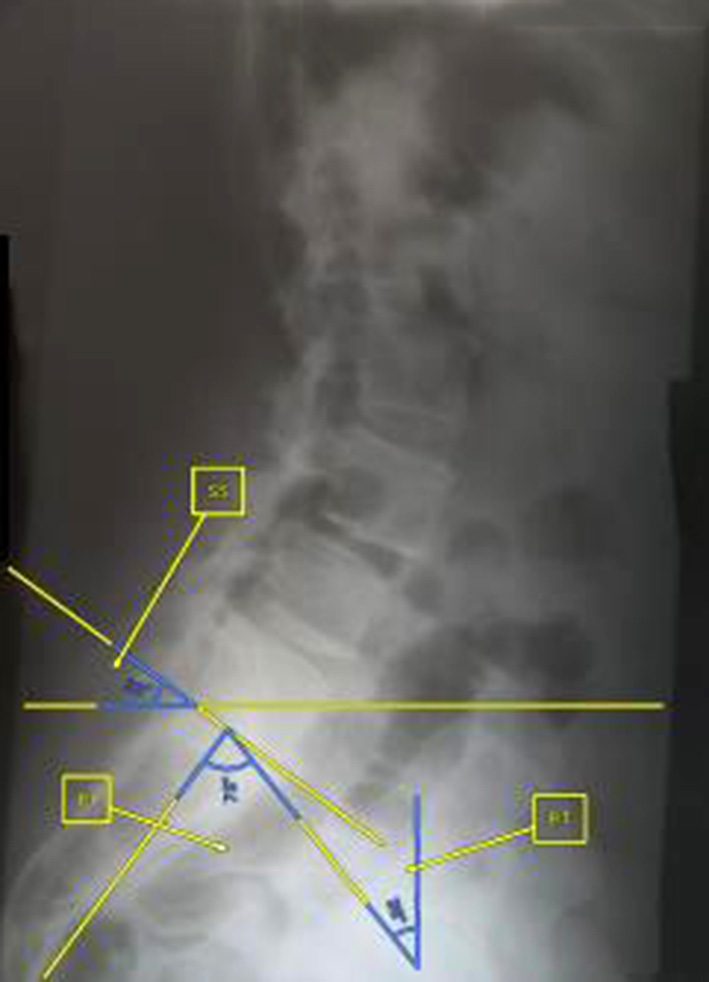

The clinical study involved 21 patients (15 women and 6 men), aged 32 to 68 years (median age – 56 (50; 65) years), divided into three groups: study group (n=4), where the author's technique of MIPIVS was applied (patent application No. a202302383 of 18.05.2023) (Fig. 3); comparison group (n=10), where the standard MIPIVS technique was used (Fig. 4); control group (n=7), where other interbody fusion techniques were employed (Fig. 5) .

Fig. 5. Radiographic control before and after surgery using alternative methods of lumbar interbody spinal fusion